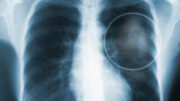

Ερευνητές του Τεχνολογικού Ινστιτούτου της Τζόρτζια των ΗΠΑ, ανέπτυξαν ένα φτηνό και μη επεμβατικό διαγνωστικό τεστ για τον καρκίνο. Το τεστ βασίζεται στην εξέταση των αερίων της εκπνοής για τον εντοπισμό πτητικών μορίων τα οποία εκλύονται όταν υπάρχει καρκίνος.

Σύμφωνα με την παρουσίαση του τεστ κατά τη διάρκεια του ετήσιου συνεδρίου της Αμερικανικής Ογκολογικής Εταιρίας στο Σικάγο των ΗΠΑ, ο εξεταζόμενος καλείται να εκπνεύσει μέσα σε ένα πλαστικό δοχείο, το οποίο σφραγίζεται και αποστέλλεται στο εργαστήριο. Για την εξέταση του περιεχομένου αξιοποιούνται τεχνικές όπως η χρωματογραφία αερίων και η φασματογραφία μάζας.

Προς το παρόν, οι ερευνητές εξετάζουν τις δυνατότητες του τεστ. Εξετάζοντας για 300 διαφορετικά πτητικά μόρια στην εκπνοή 20 υγιών γυναικών και 20 γυναικών που μόλις είχαν διαγνωστεί με καρκίνο του μαστού και δεν είχαν λάβει ακόμη θεραπεία, οι ερευνητές μπόρεσαν να εντοπίσουν τις ασθενείς με ποσοστό επιτυχίας που ανέρχεται στο 78%.

Επόμενοι στόχοι των ερευνητών είναι αρχικώς να περιορίσουν τον αριθμό των μορίων που θα πρέπει να εξετάζονται κάθε φορά (να εντοπίσουν δηλαδή τα πτητικά μόρια που είναι περισσότερο δηλωτικά του καρκίνου) και στη συνέχεια να αρχίσουν ευρείες κλινικές δοκιμές.

Εφόσον οι κλινικές δοκιμές αποδείξουν την ικανότητα του τεστ να εντοπίζει με ακρίβεια τις ασθενείς με καρκίνο του μαστού, το φθηνό και εύχρηστο αυτό τεστ θα μπορούσε να χρησιμοποιηθεί για την εξέταση του γενικού πληθυσμού. Οι ερευνητές επισημαίνουν ότι το τεστ δεν θα αντικαταστήσει τη μαστογραφία, αλλά θα παρέχει μια πρώτη ένδειξη για το ποιες γυναίκες τη χρειάζονται, πράγμα πολύ σημαντικό ιδιαίτερα σε υπό ανάπτυξη χώρες.